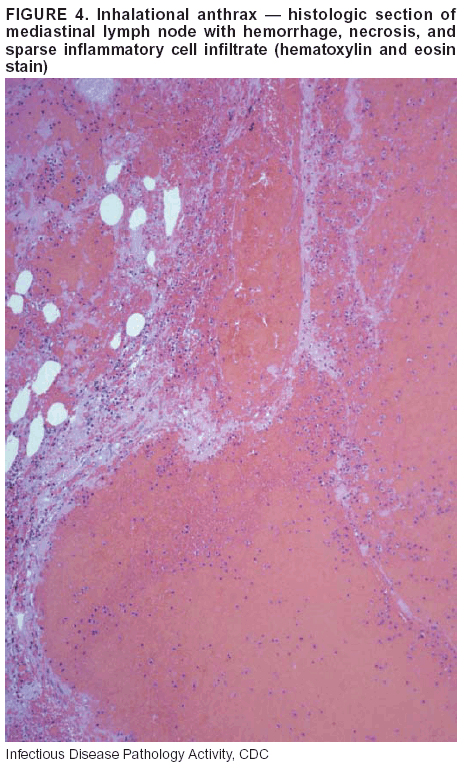

Pathologic Findings. Anthrax has three pathologic forms. Cutaneous anthrax is characterized by an eschar that forms where the bacteria entered the skin (Figure 2). Microscopically, the epidermis has necrosis and crusts, whereas the dermis demonstrates necrosis, edema, hemorrhage, perivascular inflammation, and vasculitis. The lymph nodes that drain the skin site eventually become enlarged, necrotic, and hemorrhagic. Gastrointestinal anthrax is distinguishable by hemorrhagic ulcers in the terminal ileum and caecum accompanied by mesenteric hemorrhagic lymphadenitis and peritonitis. Inhalational anthrax is characterized by hemorrhagic mediastinal lymphadenitis (Figure 3) accompanied by pleural effusions. Histologically, lymph nodes have abundant edema, hemorrhage, and necrosis with limited inflammatory infiltrate (Figure 4) (18,25--29). As any of the three anthrax forms progresses, the bacteria can spread to abdominal organs, producing petechial hemorrhages, and to the central nervous system, producing hemorrhagic meningitis (i.e., cardinal's cap) (Figure 5).

Diagnostic Specimens. Performing a complete autopsy with histologic sampling of multiple organs will help determine the distribution of bacilli and the portal of entry. The specimens that harbor the highest number of B. anthracis organisms vary by the pathologic form of anthrax. For example, diagnosis of cutaneous anthrax requires skin samples from the center and periphery of the eschar, whereas for inhalational anthrax, pleural fluid cell blocks, pleura tissue, and mediastinal lymph nodes have the highest amounts of bacilli and antigens.

Diagnostic Tests. If the patient has not received antibiotics, bacilli can be observed in tissues with H&E, Gram, and silver impregnation stains and IHC assays (Figures 6 and 7). However, after antibiotic treatment has been instituted, only silver stains and IHC assays will highlight the bacilli. IHC assays for B. anthracis can demonstrate bacilli, bacillary fragments, and granular bacterial fragments in formalin-fixed tissues, even after 10 days of antibiotic treatment. Although a DFA test is available for B. anthracis, it is not used on formalin-fixed tissues.